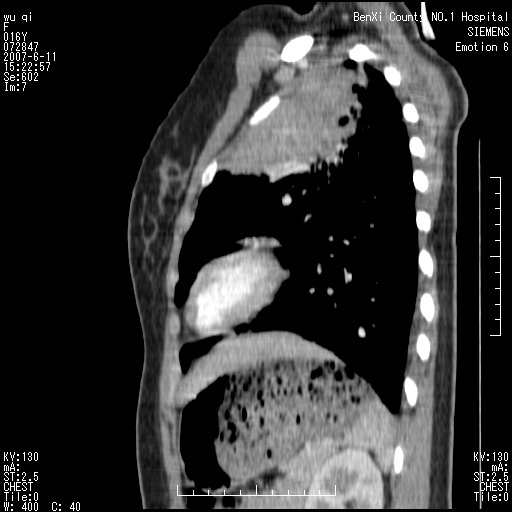

女.16、咳嗽、乏力、消受,食欲差,一个月余,无咯血,一个月前有发热。经抗炎治疗发热消失,仍咳嗽。平扫ct值34-45hu,增强后60-78hu明显强化,另外为了大家方便阅片,简单提下自己意见,纵隔内淋巴结肿大,左肺片影,其内密度不均,增强扫描明显强化,左肺上叶支气管可见支气管气象。尖段闭塞。冠状位可见左侧锁骨下静脉受压下移。请大家会诊,分析。

肺不张会引起纵隔结构向患侧移位,而该病例纵隔是向右侧移位,且左侧锁骨下静脉受压移位,均提示病灶位于纵隔内。我感觉象是淋巴瘤,左肺病灶是因为阻塞性肺炎引起的。

其实这个病例平扫我和大家的诊断一样,考虑为肺结核,加上相似的症状。增强后我发现原来左侧的锁骨下静脉受压下移,

1。所以能不能就是肺外的病变呢?并且是实性的肿物。只有肺外的实性病变可以把锁骨下静脉压迫到如此地步?当然,结核可以粘联,可是谁见过结核如此可怕的牵拉作用,累及到肺外大血管了。

你所说的左锁骨下静脉下移值得商榷:我认为从该血管的走形和增强的密度上看,应该是左肺动脉弓发出的分支,从病变形态上看,好像囊实性病变,从强化特点上看还是考虑炎性改变。

看过病例,肿块位于左侧胸膜顶和上纵隔,呈巨大不规则形软组织密度,边缘不清楚,和上纵隔诸结构不好分界,并可见肿大淋巴结影,左上叶支气管尚通畅,但上叶肺组织可见压迫性不张和膨胀不良。肿块内部可见一条明显的粗大血管影,经多层面追踪,应该是左侧锁骨下静脉。从以上表现来看,肿块的起源应该是在肺外,大致来源于胸膜顶部,向下、内生长。增强扫描,肿块内部可见多发血管分支,证明肿块血供较为丰富,从这一点上,比较符合间叶组织来源的恶性肿瘤,淋巴瘤往往表现为多发肿大淋巴团,但增强扫描内部出现迂曲血管的几率比较低,我觉得不是太象。间叶组织类别非常多,该类肿瘤只靠影像学很难鉴别,经皮穿刺活检不失为最好的方法,可以首先考虑。

定位定性理由:1 斜裂到哪里去了?明显的前上移位了.2 原"左上肺区域"透光度明显增高,肺纹稀疏,为肺气肿征象.3不是全上肺不张,而为固有上叶,可惜楼主的冠位图未明显显示.4 左下肺背段可见结节灶,紧贴脊柱旁,再仔细看看.5 胸膜改变显示支持是炎性病变.6那根血管我也仔细观察了,浓度同动脉,近端较粗,应为肺动脉,包括实变肺内的血管分支都应为肺动脉分支.7 实变内明显不均强化,更加支持炎性病变.8淋巴结肿大以弓旁为主,轻度均匀强化,中纵隔内未见明显淋巴结,面此区的淋巴肿最多见于结核;9实变近端无明显块影而不支持腔内肿瘤,虽然无典型的支气管狭窄直接征象.10 为什么纵隔向患侧移位不明显?因为肺容积缩小不是太显著,更多的是肺泡内较多渗出导致如此.11 实变外围的条片影从形态看不象纵隔肿瘤所致的压迫性肺炎,如为压迫应紧绕肿块环形分布.14 与纵隔结构有明显分界,而且从重组图像看病灶主体更象楔变而非肿块,有哪一种肿瘤可以导致下缘如此平直?